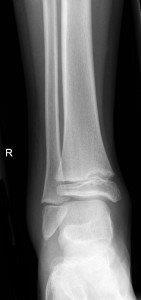

Toddler's fracture

Toddler's fractures

• Follow up Orthopaedic Fracture Clinic in 1 week.